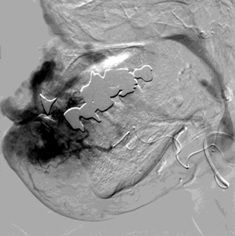

腹腔动脉造影也未发现出血 |

第二天病人持续出血,发现胰横动脉分支供血的部位出血(在PTCD管的左侧) |

选择性胰背动脉造影未见危险分支 |

微导管进入胰背动脉造影 |

注射n-BCA |

术后造影 |